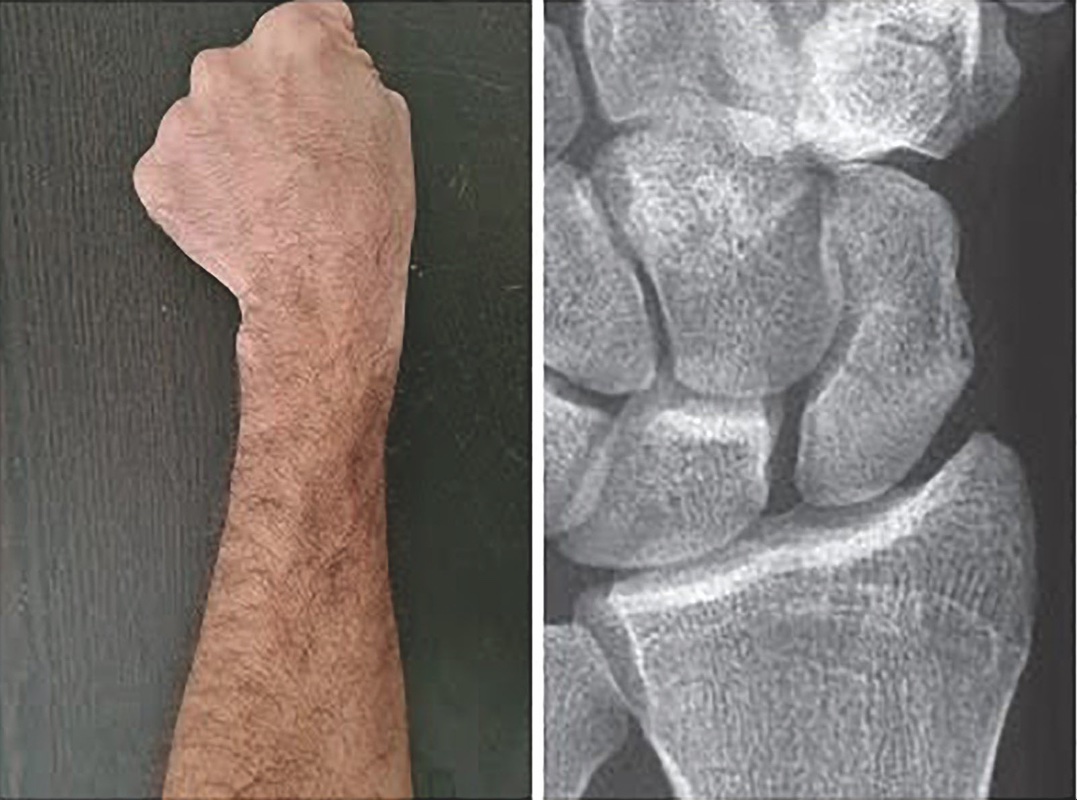

ESAME OBIETTIVO

La frattura di scafoide deve essere sempre sospettata in caso di dolore in regione carpale/radiale. Le tre parti dello scafoide (terzo medio 70% delle fratture, polo prossimale 20% delle fratture, polo distale/tubercolo 10% delle fratture) devono essere palpate separatamente. La sensibilità dei test clinici è molto alta (fino al 100% in caso di positività di tutti i test) ma la loro specificità è bassa (Fig. 2 A, B, C).